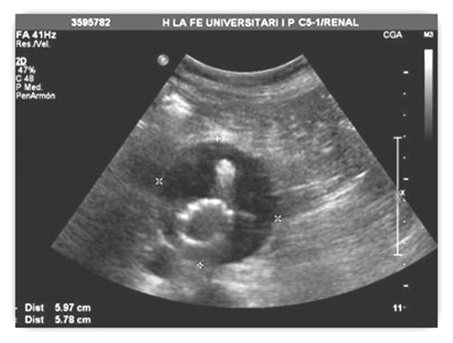

El paciente se coloca en decúbito supino y se realiza en primer lugar, un barrido desde la apófisis xifoides hasta la bifurcación aórtica y ambas ilíacas con la sonda curva en modo B. Así se visualiza la posición de la endoprótesis, se valoran posible migración y se mide el diámetro máximo en el plano axial, tanto el AP como el transverso (Fig. 4). Posteriormente, se inicia la imagen doppler color de forma sistémica para objetivar endofuga de alguna rama visceral o lumbar dentro del saco aneurismático.

Fig. 4. Control del diámetro máximo de AAA tras reparación con endoprótesis

fenestrada y embolización previa con “coils” de arteria mesentérica inferior.